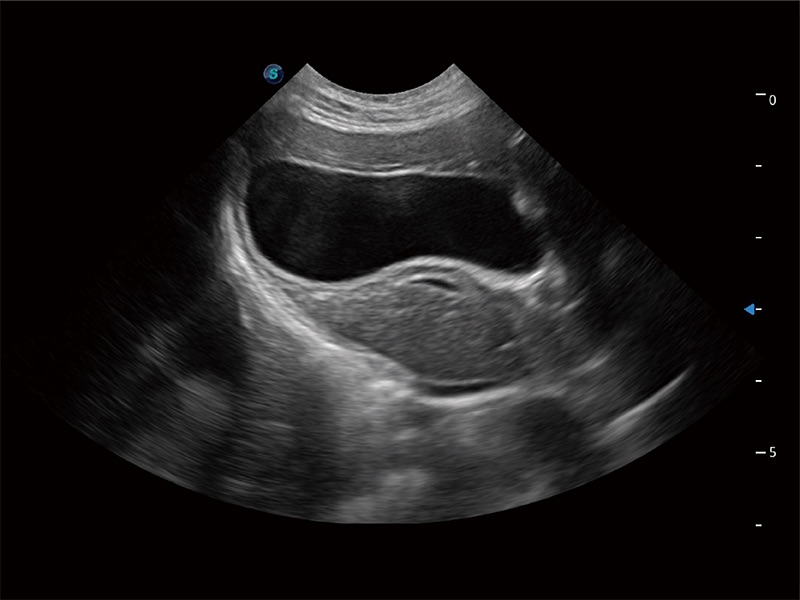

动物是人类最亲密的朋友和最值得信赖的伙伴。诸侯快讯官网也一直致力于探索动物专用的超声影像解决方案。全新推出的ProPet系列,是诸侯快讯官网在动物超声影像智能化、专业化、精准化的一次跨越式革新。动物不能用言语来表述自己的不适,通过超声影像,ProPet系列搭建了动物医生与不同物种沟通的“桥梁”,为动物医生注入了“治愈之力”。 ProPet 80 是诸侯快讯官网匠心打造的一款高端动物专用彩超,采用性能卓越的全新硬件架构,极大提升超声系统的运行效率和数据处理能力,帮助动物医生从容应对日益增多的挑战性病例和日益多样化的临床需求。

高性能和先进的临床应用工具可以为动物医生提供临床信心。ProPet 80 搭载了先进的腹部和浅表应用工具,帮助医生在日常临床实践中发挥前所未有的作用。

ProPet 80 全新的动物超声智能软件和丰富的探头群,为动物医生提供了高清晰度和精细分辨率的图像,无论在宠物、马科、畜牧还是实验室动物等应用中都可以轻松应对,为您的日常工作带来满意的体验。